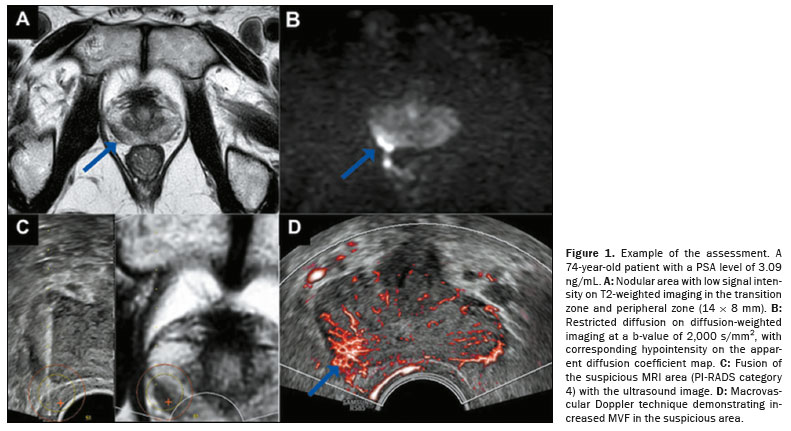

Patients were placed in the left lateral position under anesthesia. Systematic biopsy was performed with 10 cores using an 18-G tru-cut needle via the transrectal route. The MRI scans (minimum 1.5-T) were fused with real-time ultrasound images acquired by using a high-resolution ultrasound system (RS85 Prestige; Samsung Medison Co Ltd, Seoul, South Korea). Microvascular Doppler ultrasound was applied to the MRI-identified suspicious area (Figure 1). All procedures were performed by an operator with over 15 years of experience.